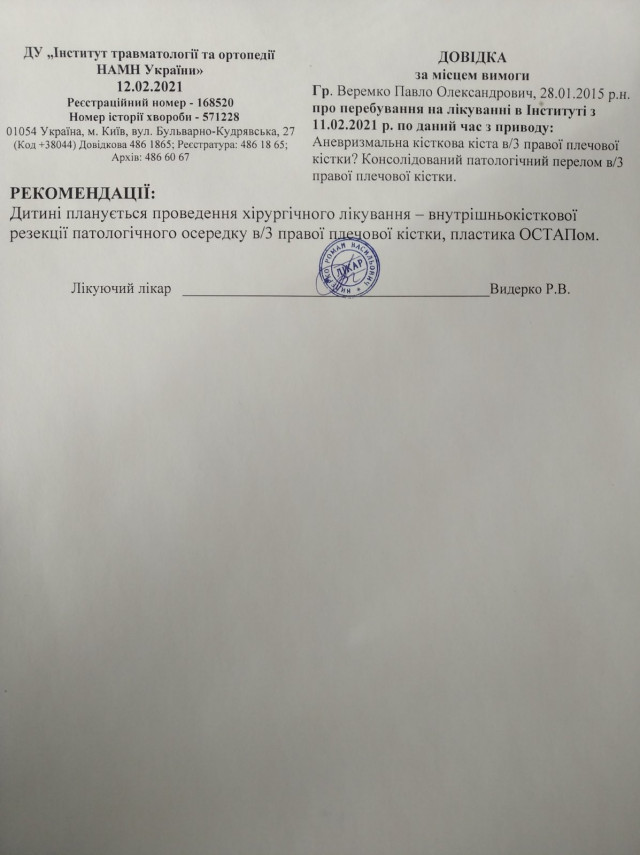

Шестирічному Павликові Веремку з прикордонного села Борового, що на Любомльщині (нині Ковельський район), встановили непростий діагноз – аневризмальна кісткова кіста правої плечової кістки, консолідований патологічний перелом правої плечової кістки. На хлопчика чекає складна операція із видалення частини ураженої кістки та довга реабілітація.

Наразі Сніжана з Павликом перебувають у Києві в Інституті травматології та ортопедії НАМН України. Хлопчика обстежують і готують до операції. А вона – недешева. Крім того, чималі кошти потрібні й на подальше лікування та реабілітацію. І самим їм не впоратися. Бо сума для родини, яка живе в селі й має мізерний дохід, направду непідйомна.